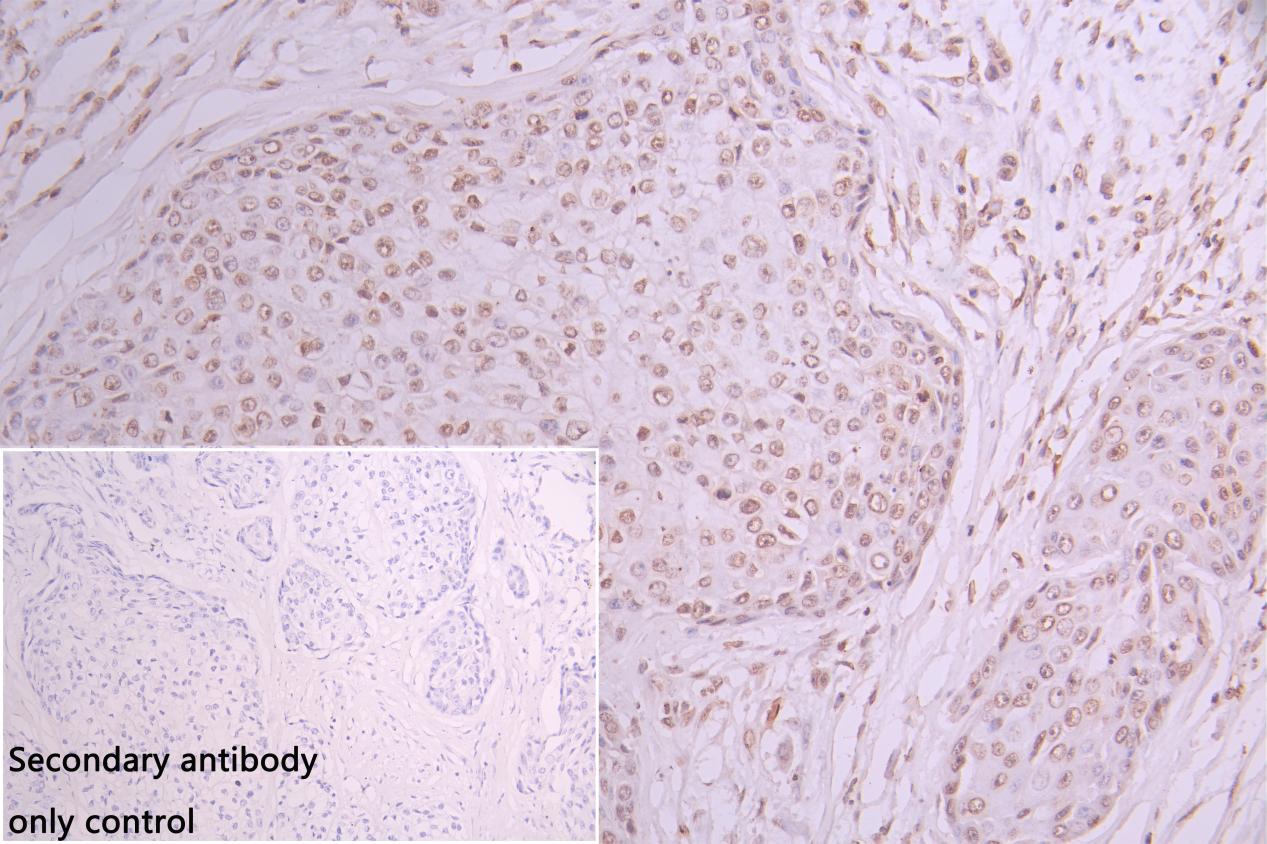

• IHC image of CSB-PA010289ESR1HU diluted at 1:30 and staining in paraffin-embedded human pancreatic cancer performed on a Leica BondTM system. After dewaxing and hydration, antigen retrieval was mediated by high pressure in a citrate buffer (pH 6.0). Section was blocked with 10% normal goat serum 30min at RT. Then primary antibody (1% BSA) was incubated at 4°C overnight. The primary is detected by a Goat anti-rabbit polymer IgG labeled by HRP and visualized using 0.05% DAB. Secondary antibody only control: uses 1% BSA instead of primary antibody

• IHCimageofCSB-PA010289ESR1HUdilutedat1:30andstaininginparaffin-embeddedhumancolorectalcancerperformedonaLeicaBondTMsystem.Afterdewaxingandhydration,antigenretrievalwasmediatedbyhighpressureinacitratebuffer(pH6.0).Sectionwasblockedwith10%normalgoatserum30minatRT.Thenprimaryantibody(1%BSA)wasincubatedat4°Covernight.TheprimaryisdetectedbyaGoatanti-rabbitpolymerIgGlabeledbyHRPandvisualizedusing0.05%DAB. Secondaryantibodyonlycontrol: uses 1%BSA instead of primary antibody